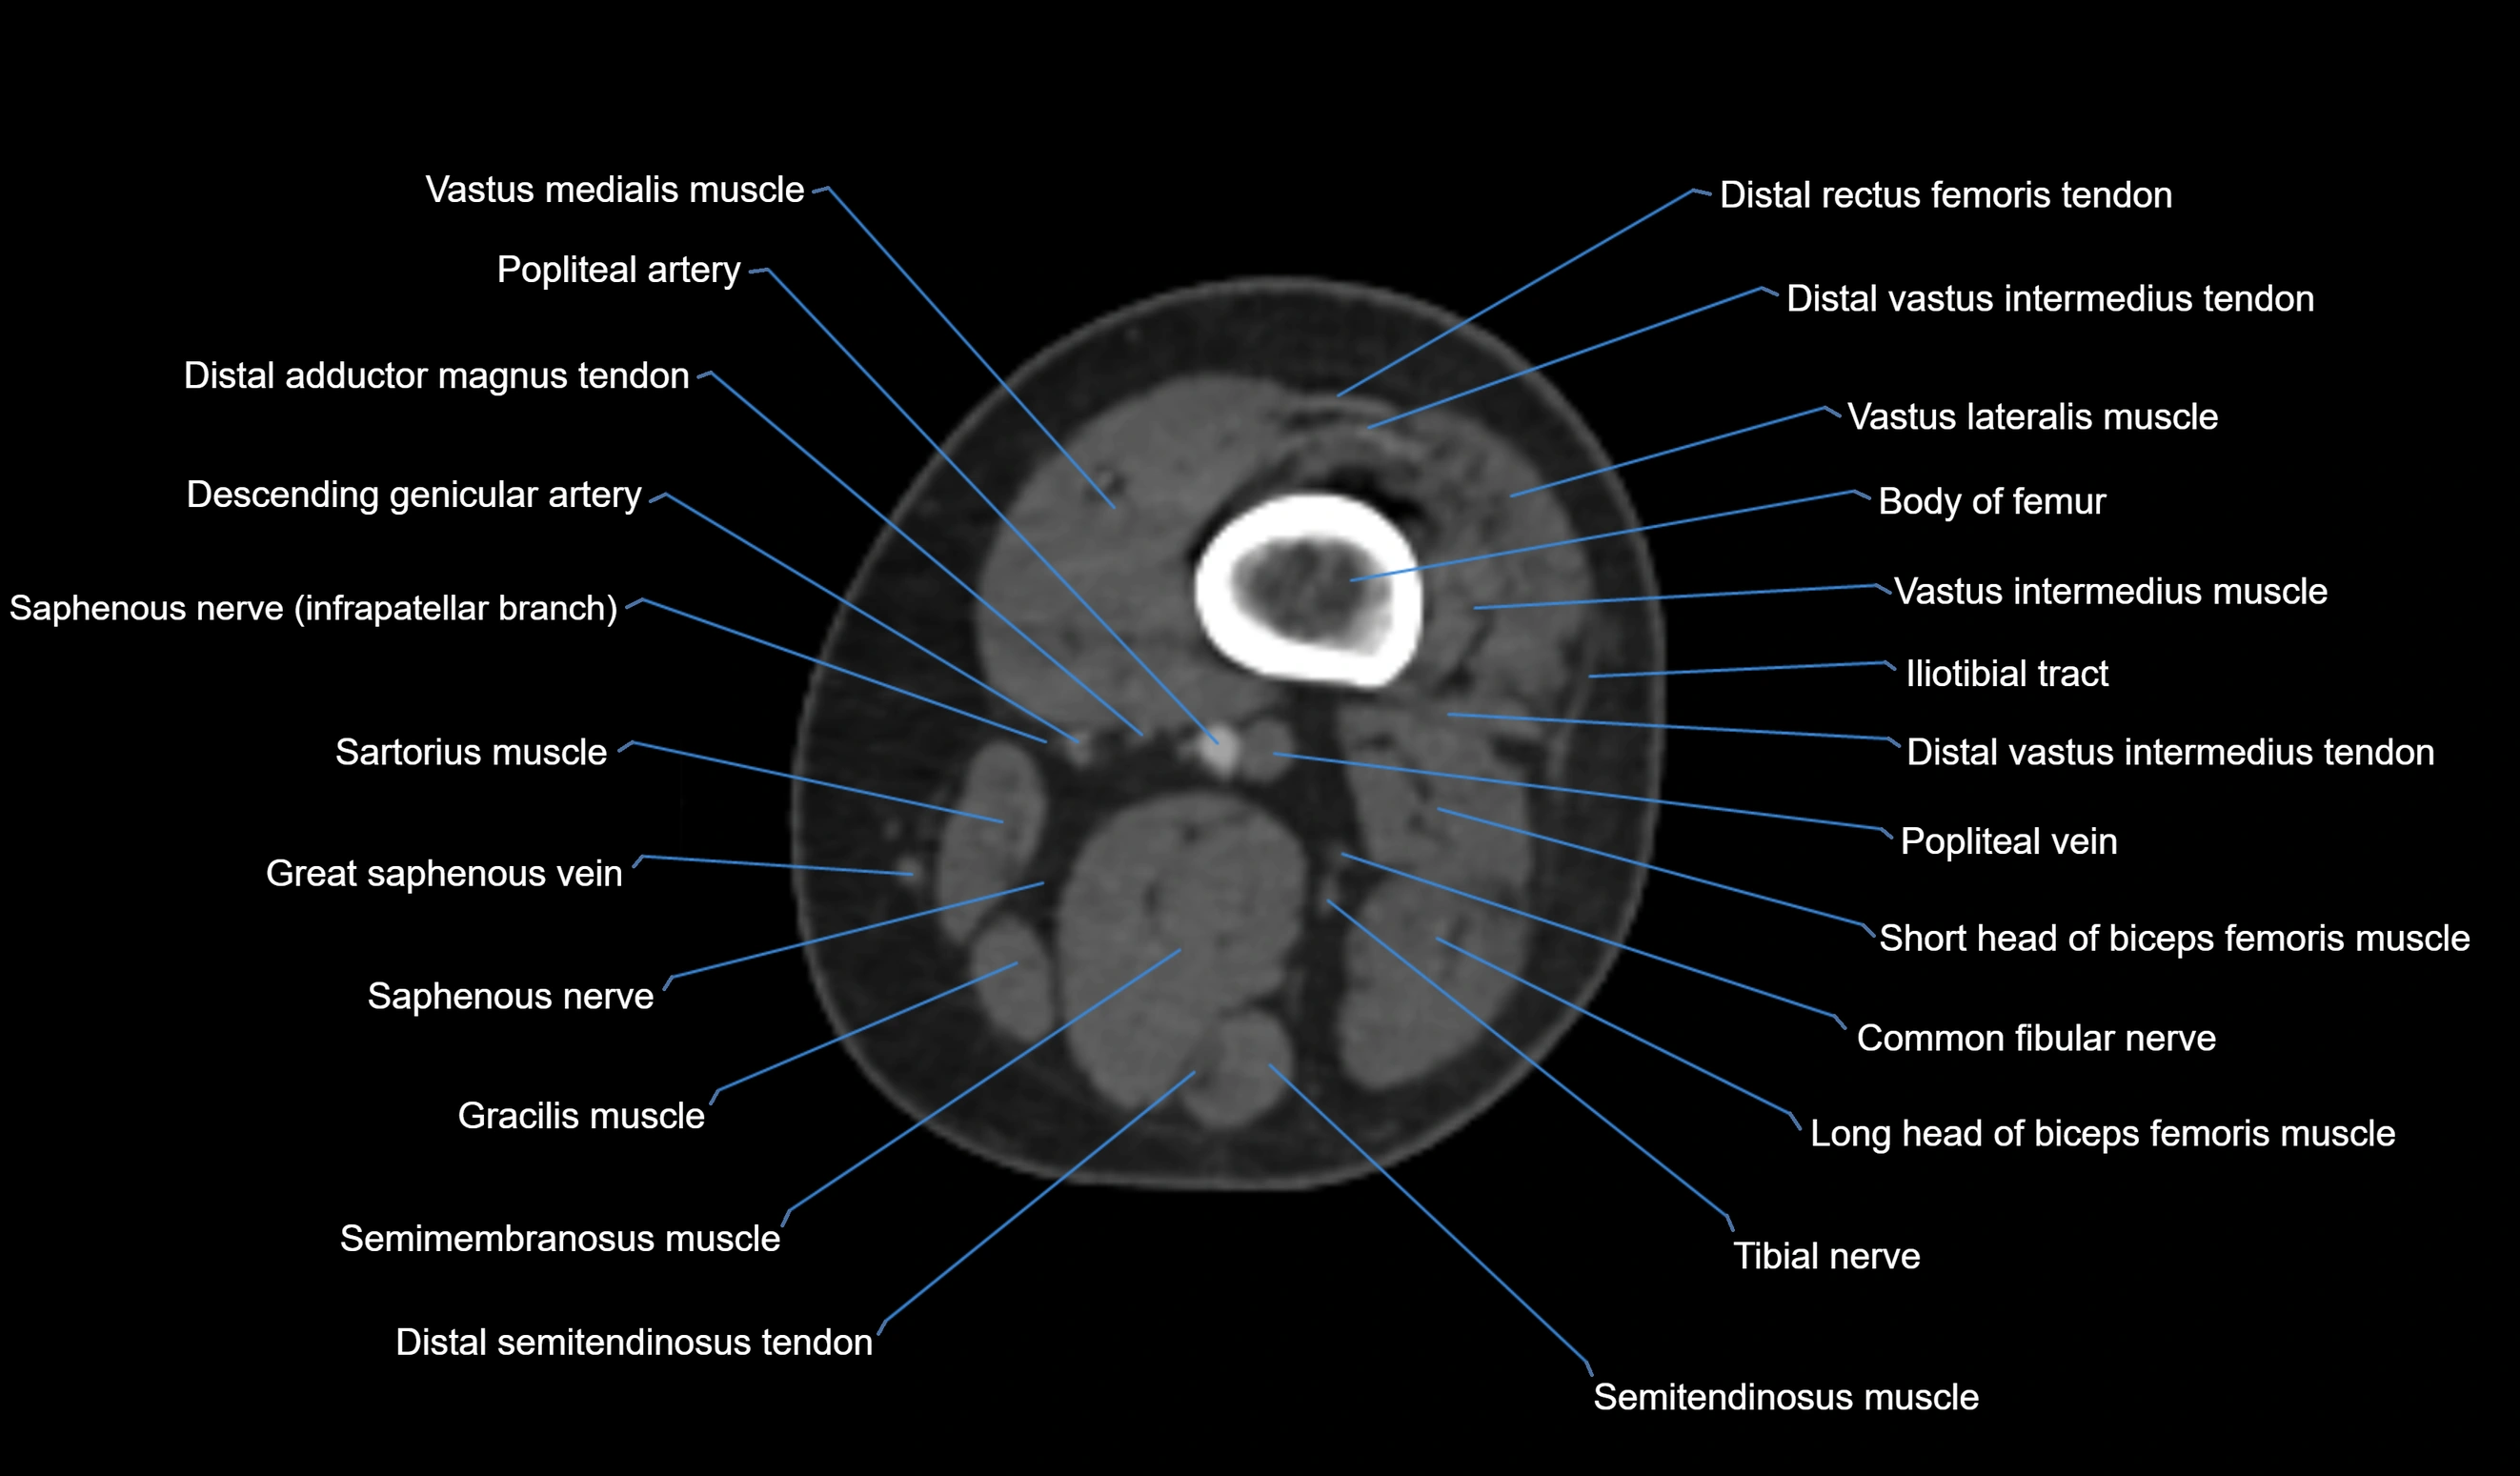

- Body of femur

- Common fibular nerve

- Descending genicular artery (Articular branches)

- Distal adductor magnus tendon

- Distal rectus femoris tendon

- Distal semitendinosus tendon

- Distal vastus intermedius tendon

- Popliteal artery

- Popliteal vein

- Saphenous nerve

- Sartorius muscle

- Semitendinosus muscle

- Tibial nerve

- Vastus lateralis muscle

- Vastus medialis muscle